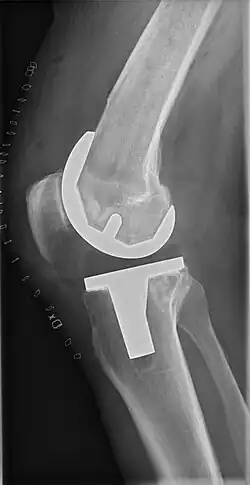

Knee replacement, also known as knee arthroplasty, is a surgical procedure to replace the weight-bearing surfaces of the knee joint to relieve pain and disability, most commonly offered when joint pain is not diminished by conservative sources.[1][2] It may also be performed for other knee diseases, such as rheumatoid arthritis. In patients with severe deformity from advanced rheumatoid arthritis, trauma, or long-standing osteoarthritis, the surgery may be more complicated and carry higher risk. Osteoporosis does not typically cause knee pain, deformity, or inflammation, and is not a reason to perform knee replacement.

Knee replacement surgery can be performed as a partial or a total knee replacement.[3] In general, the surgery consists of replacing the diseased or damaged joint surfaces of the knee with metal and plastic components shaped to allow continued motion of the knee.

Femoral replacement

A round-ended implant is used for the femur, mimicking the natural shape of the joint. On the tibia the component is flat, although it sometimes has a stem that goes down inside the bone for further stability. A flattened or slightly dished high-density polyethylene surface is then inserted onto the tibial component so the weight is transferred metal to plastic, not metal to metal. During the operation any deformities must be corrected, and the ligaments balanced so the knee has a good range of movement, and is stable and aligned. In some cases the articular surface of the patella also is removed and replaced by a polyethylene button cemented to the posterior surface of the patella. In other cases, the patella is replaced unaltered.